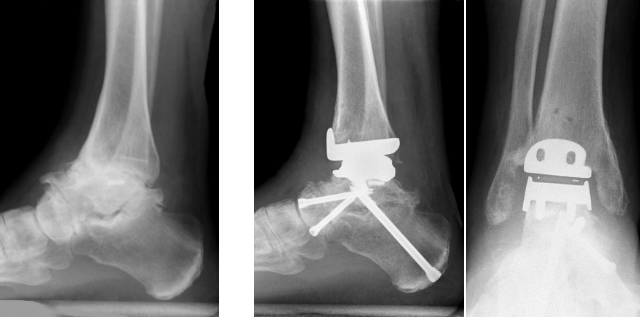

Versteifung des unteren Sprunggelenkes mit gleichzeitiger Versteifung des Chopartgelenks und Prothese des oberen Sprunggelenkes

Das untere Sprunggelenk wird häufig gleichzeitig mit dem medialen (Double Arthrodese) und lateralen Chopartgelenk (Triple-Arthrodese) versteift und korrigiert. Aufgrund der komplexen Anatomie sollten allfällige Fehlstellungen immer mitkorrigiert werden. Geschieht dies unzureichend, wird eine Revisionsoperation notwendig. Dabei muß unbedingt die Fehlstellung korrigiert werden, gelegentlich sind auch hier Defektauffüllungen mit Knochenmaterial durchzuführen. Die Nachbehandlung erfolgt auf jeden Fall für 10-12 Wochen mittels Unterschenkelgipsen.